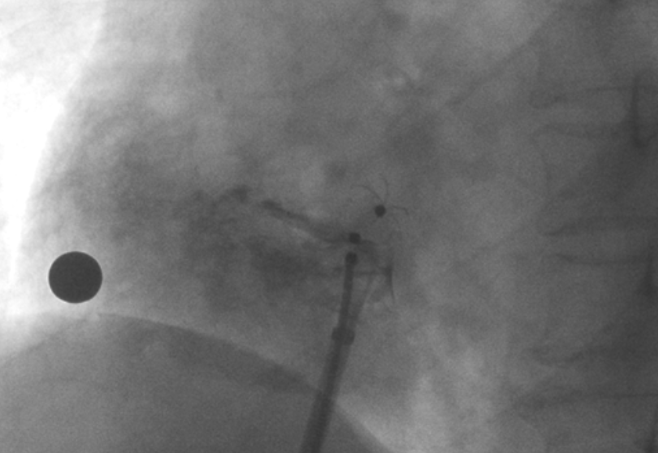

造影顯示PFO封堵完全,無殘余分流, 試驗器械充分舒展并貼合良好

術中造影顯示患者為PFO且長隧道型,目前市場上已商業化的PFO封堵器難以滿足該患者解剖結構封堵需求。迪創醫療自主研發的OmniSeal PFO封堵器自適應性雙盤貼合設計能廣泛適應不同PFO隧道長度的解剖結構和形態,其雙盤外包覆式阻流和隧道內填充阻流相結合的雙重阻流設計,可為此患者實現有效封堵。與此同時,OmniSeal首創的完全可穿刺式設計,也為此患者最大程度地保留了房間隔區域穿刺通道,以實現全兼容未來可能的左心系統二次介入術。術終造影和心臟超聲顯示封堵完全、效果良好。作為OmniSeal的首例臨床應用,本次手術的順利完成和優異效果充分體現了產品的設計創新優勢。